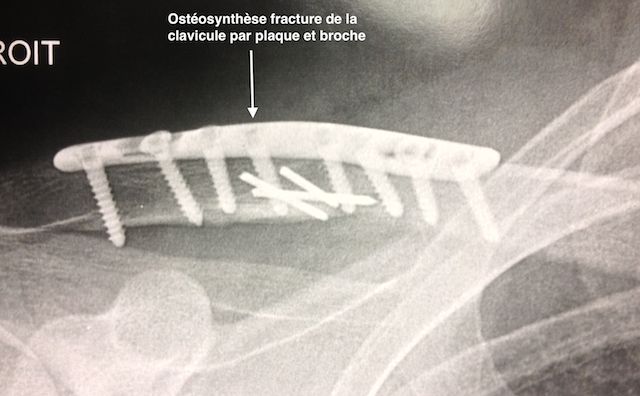

Lorsque qu’avec les anneaux, la fracture n’est pas réductible en longueur, on peut proposer une intervention chirurgicale dont le but est de réduire la fracture en mettant en place une plaque.

Ceci va redonner la bonne longueur à la clavicule, mais moyennant un risque chirurgical et une cicatrice qui n’existe pas si l’on n’opère pas.

Ostéo-synthèse d'une fracture de la clavicule

Figure 4 : Ostéo-synthèse d'une fracture de la clavicule